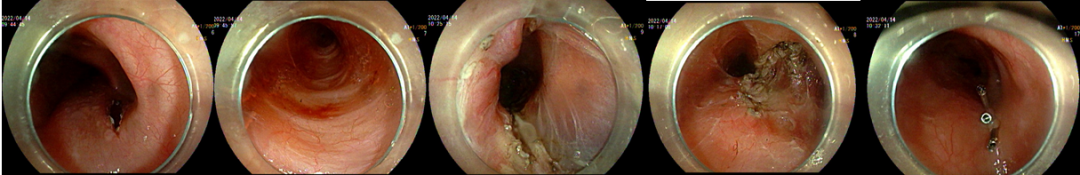

在向韩梅详细讲解了手术方案及可能出现的风险后,她和家属均表示理解及充分信任,手术团队准备为她实施贲门失弛缓POEM内镜下肌切开术+食管中段憩室STESD(隧道内镜下憩室切开术)。手术由肖绪华医生主刀,手术进展顺利,耗时约60分钟,韩梅的两个主要病症在一次内镜手术下都迎刃而解。

POEM操作

(上:POEM示意图,下:对应的内镜下所见)

1.粘膜层切开;2.分离粘膜下层,建立粘膜下隧道;

3.肌切开4.憩室脊切开;5.钛夹止血处理。